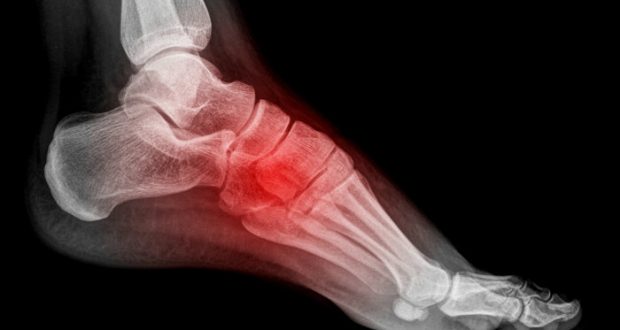

Os ossos afetados pela fratura por estresse

A condição pode atingir todos os tipos de ossos, entretanto, os mais atingidos são aqueles que suportam o peso corporal, com destaque para os membros inferiores.

A mestra em ortopedia e traumatologia, Ana Paula Simões, relatou que pesquisas realizadas com corredores indicaram que os ossos que mais sofrem com o problema são: a tíbia, os metatarsos, a fíbula, o fêmur e o navicular.

O diagnóstico pode ser determinado por meio de exames físicos, histórico médico, exames de raio-X, escaneamento ósseo e exames de imagem por ressonância magnética.